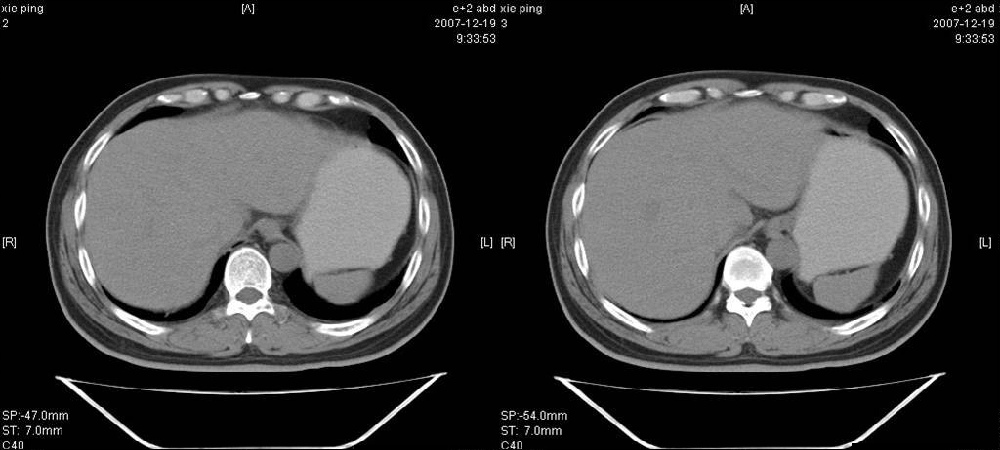

临床病史:患者,男,53岁,因反复上腹部饱胀不适2+月,在餐后或饥饿时明显,伴呃逆,无呕吐、呕血,无腹痛腹泻;2年前腹腔镜胆囊切除,否认肝炎、结核等病史。

体格检查:一般情况可,腹平软,全腹无压痛,无反跳痛,未扪及包块,肝脾未及,肠鸣音正常。白细胞6.03×10e9/l,中性粒细胞3.32×10e9/l,淋巴细胞2.06×10e9/l

胰腺头部低密度囊性病灶,边缘清楚,增强后囊壁略强化。考虑:胰头假性囊肿!

胰腺头部(或肝脏尾叶部)低密度囊性病灶,边缘清楚,增强后囊壁略强化。考虑:胰头假性囊肿. 或肝脏尾叶部囊肿。

考虑十二指肠憩室。从影像上看,病变位于下腔静脉前胰头后方十二指肠内侧,肝尾叶受压,说明病变来源于后腹膜;胰胆管成像胰管和胆道未见扩张,总胆管中段受压未显示,上下段正常,所以不考虑来源与于肝尾叶和总胆管的囊肿。考虑为十二指肠憩室或小网膜囊肿。

楼上高手,本例的确是一例十二指肠憩室.